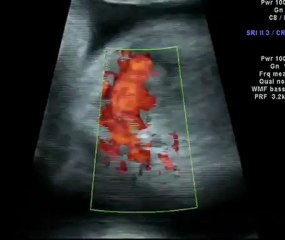

Aneurisma dell'arco aortico, a Modena protesi mai vista in Italia